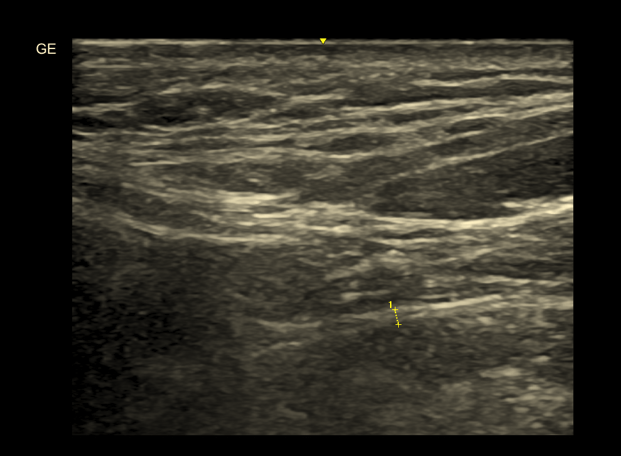

2. Wzmożone napięcie mięśniowe – czy USG ma znaczenie?

Szumy uszne mogą mieć podłoże somatosensoryczne. Nadmierne napięcie mięśni żucia i szyi wpływa na percepcję dźwięku.

Diagnostyka szumów usznych USG mięśni

USG pozwala ocenić:

• pogrubienie mięśni

• asymetrię

• cechy przewlekłego przeciążenia

Choć USG nie ocenia funkcji nerwowej, może wskazać strukturalne podłoże napięcia.